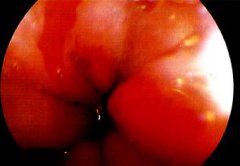

食管下段的鱗狀上皮被柱狀上皮覆蓋,因?yàn)橛薆arrett首先報(bào)道,因此稱 Barrett食管 ,中文翻譯為巴雷特食管。目前認(rèn)為是獲得性,可能與 反流性食管炎 相關(guān),并有發(fā)生 腺癌 的可能。其癥狀...

Barretts esophagus,即巴雷特食管 , 巴雷特食管因?yàn)槲改c上皮長在了食管下端,如果長的是胃上皮則可能具有分泌胃酸的能力,而食管粘膜又沒有類似于胃粘膜那樣象瓷器樣的粘膜保護(hù)層,容易引起食管粘膜的腐蝕性損...

•   Barrett食管癥狀及檢查 日期:2016-05-02 17:16:00 點(diǎn)擊:2228 好評:37

常見癥狀 便血 惡心與嘔吐 燒心 吞咽困難 胸骨后疼痛 BE本身并無癥狀,其癥狀主要是由于胃食管反流及其并發(fā)癥所引起的,多數(shù)患者最初有GERD癥狀,如胃灼熱,反流,吞咽困難,常見癥狀多見...